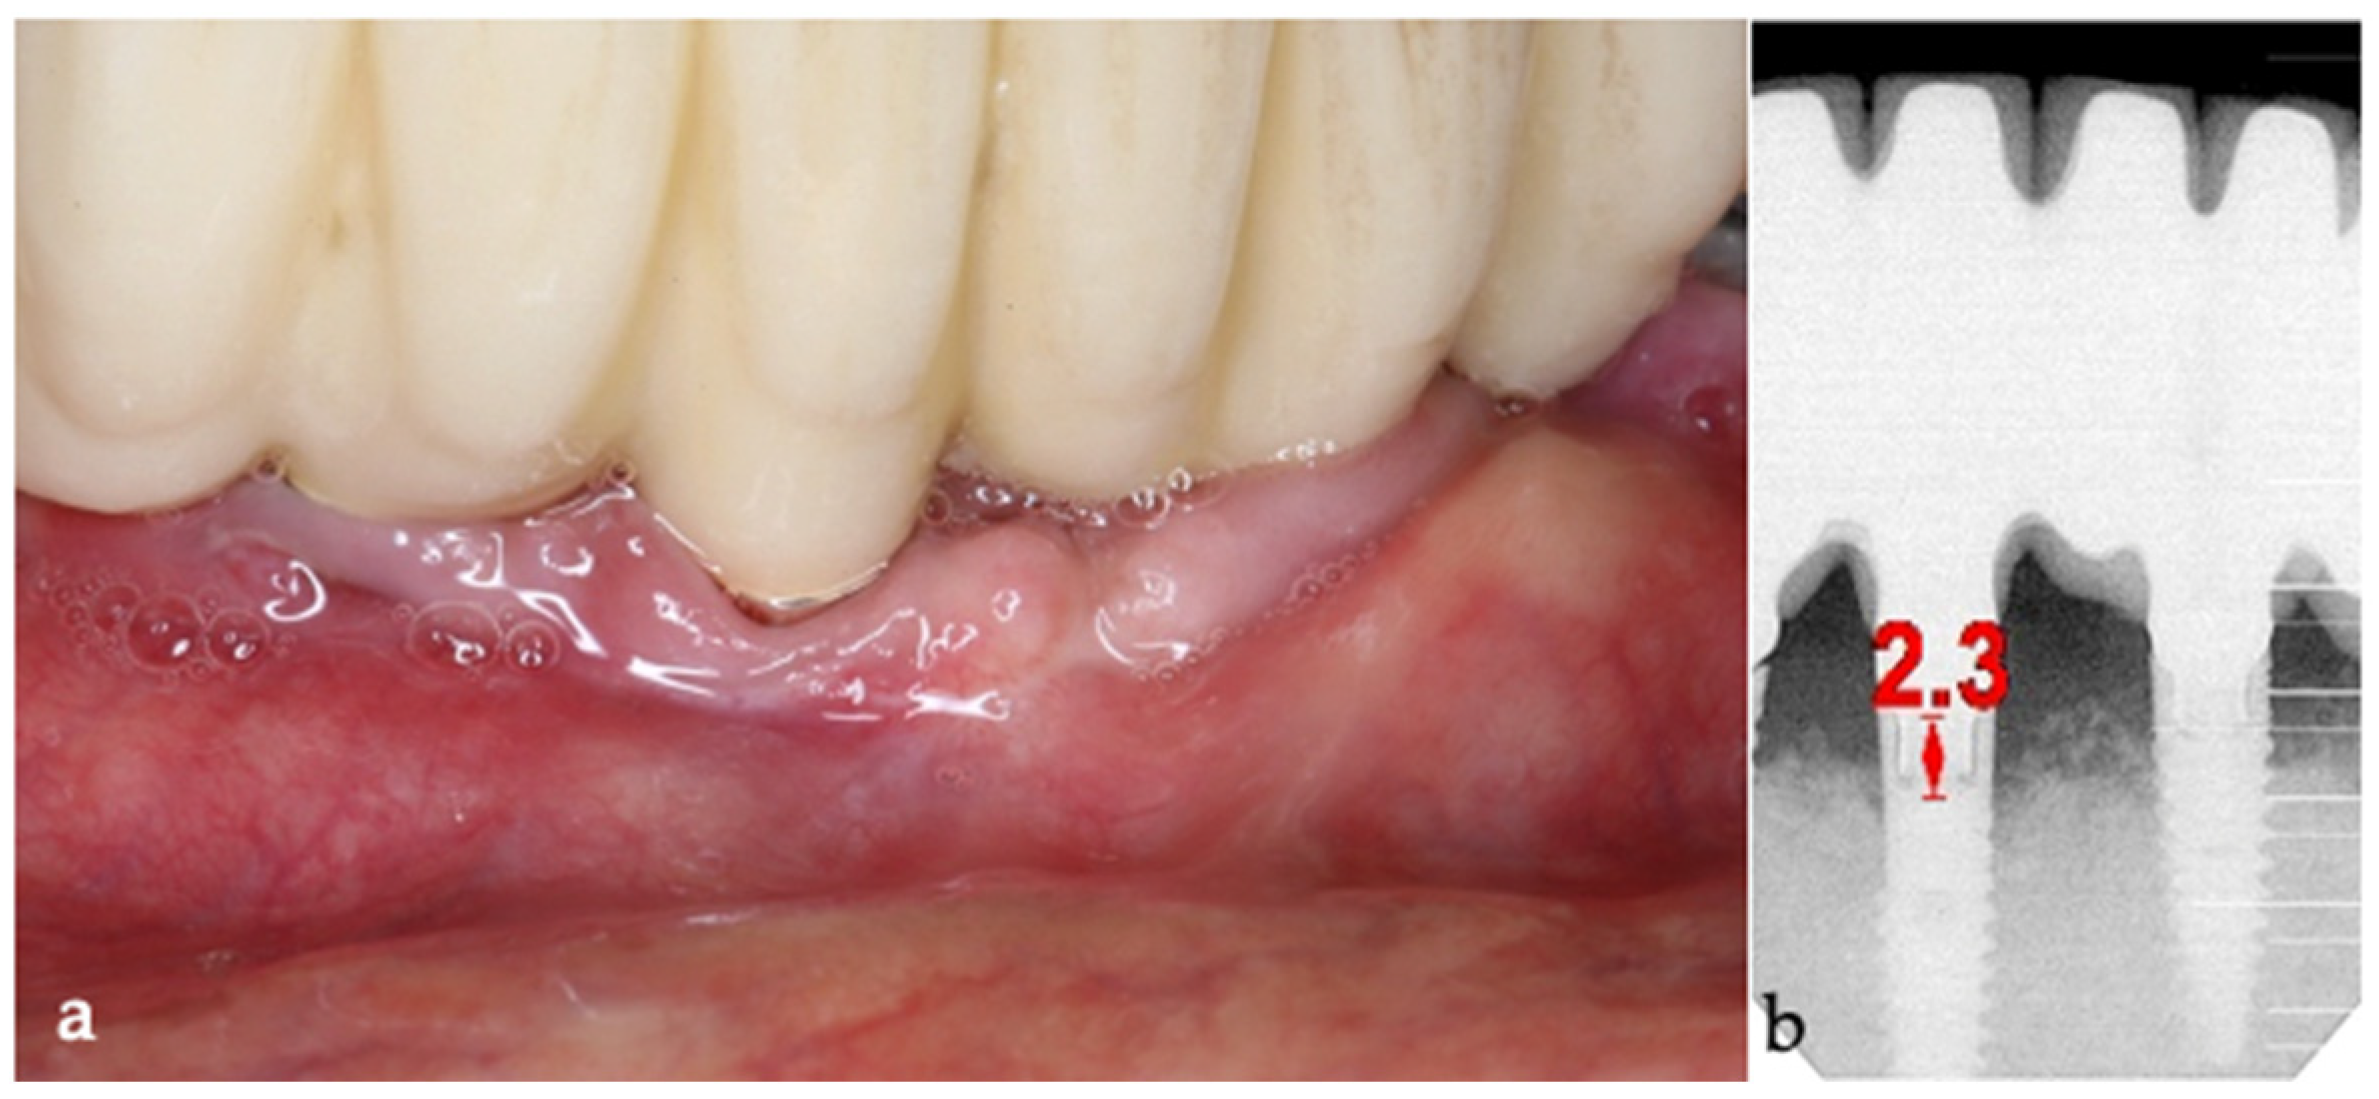

A generally healthy 63-year-old female presented to our clinic with chief complaints of foul odor and occasional pain emanating from dental implants located in the mandibular right quadrant (from implants #42 to #47). Clinical examination revealed peri-implantitis, with a high level of BoP and suppuration around the affected implants. The radiographic evaluation confirmed moderate-to-severe vertical bone loss, consistent with a diagnosis of peri-implantitis (Figure 19).

Figure 19. (a) Initial clinical assessment; (b) Periapical X-ray presenting the measurements (red arrows) from the platform to the bone; (c) The panoramic view shows the vertical bone loss found at baseline.